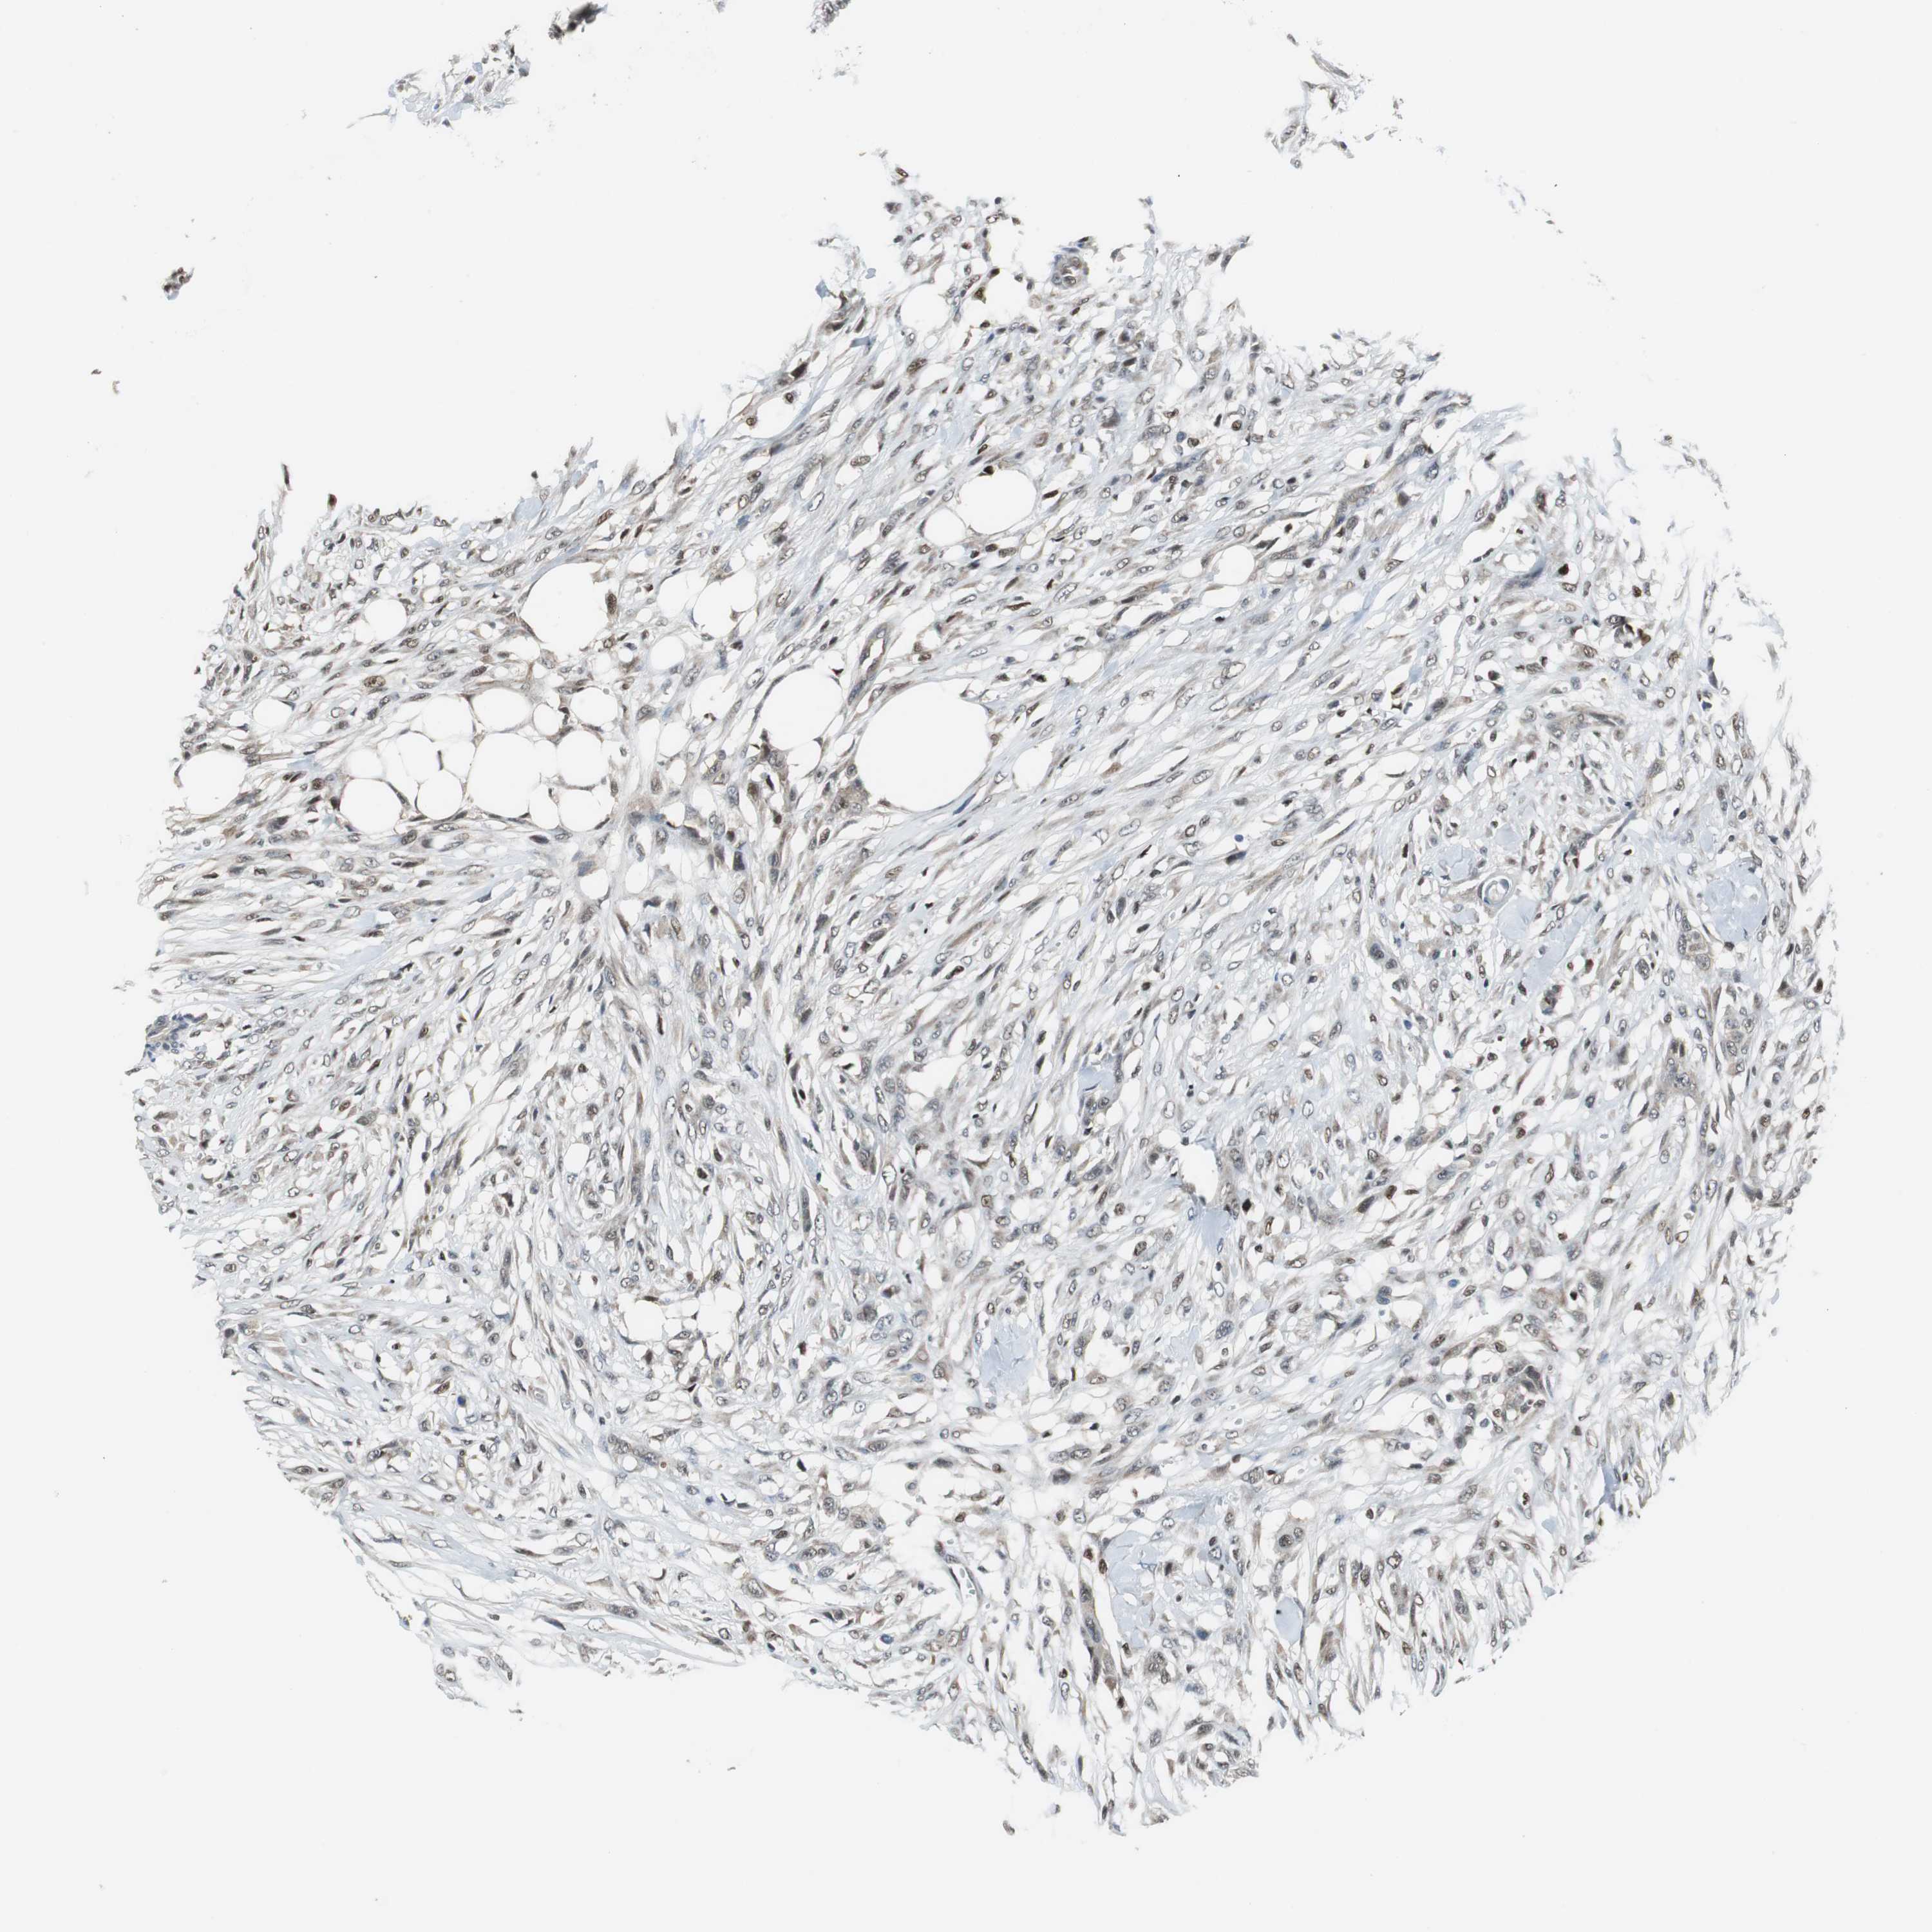

SKIN CANCER - Protein expressioni

A mouse-over function shows sample information and annotation data. Click on an image to view it in a full screen mode. Samples can be filtered based on level of antibody staining by selecting one or several of the following categories: high, medium, low and not detected. The assay and annotation is described here.

Antibody stainingi

Antibody staining in the annotated cell types in the current human tissue is reported as not detected, low, medium, or high, based on conventional immunohistochemistry profiling in selected tissues. This score is based on the combination of the staining intensity and fraction of stained cells.

Each image is clickable and will lead to virtual microscopy that enables deeper exploration of all samples and also displays staining intensity scores, fraction scores and subcellular localization as well as patient and tissue information for each sample.

Antibody HPA005653

Staining

High

Medium

Low

Not detected

Intensity

Strong

Moderate

Weak

Negative

Quantity

>75%

75%-25%

<25%

None

Location

Nuclear

Cytoplasmic/membranous

Cytoplasmic/membranous,nuclear

Squamous cell carcinoma, NOS

Basal cell carcinoma